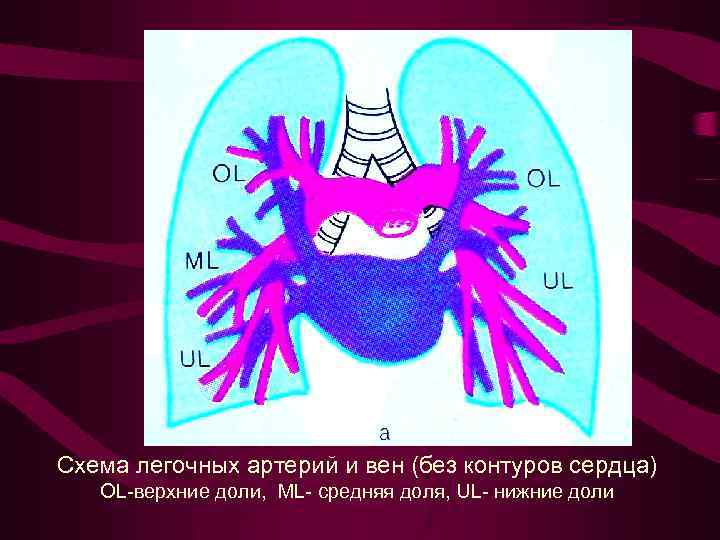

Схема легочных артерий и вен (без контуров сердца) ОL-верхние доли, ML- средняя доля, UL- нижние доли

Схема легочных артерий и вен (без контуров сердца) ОL-верхние доли, ML- средняя доля, UL- нижние доли